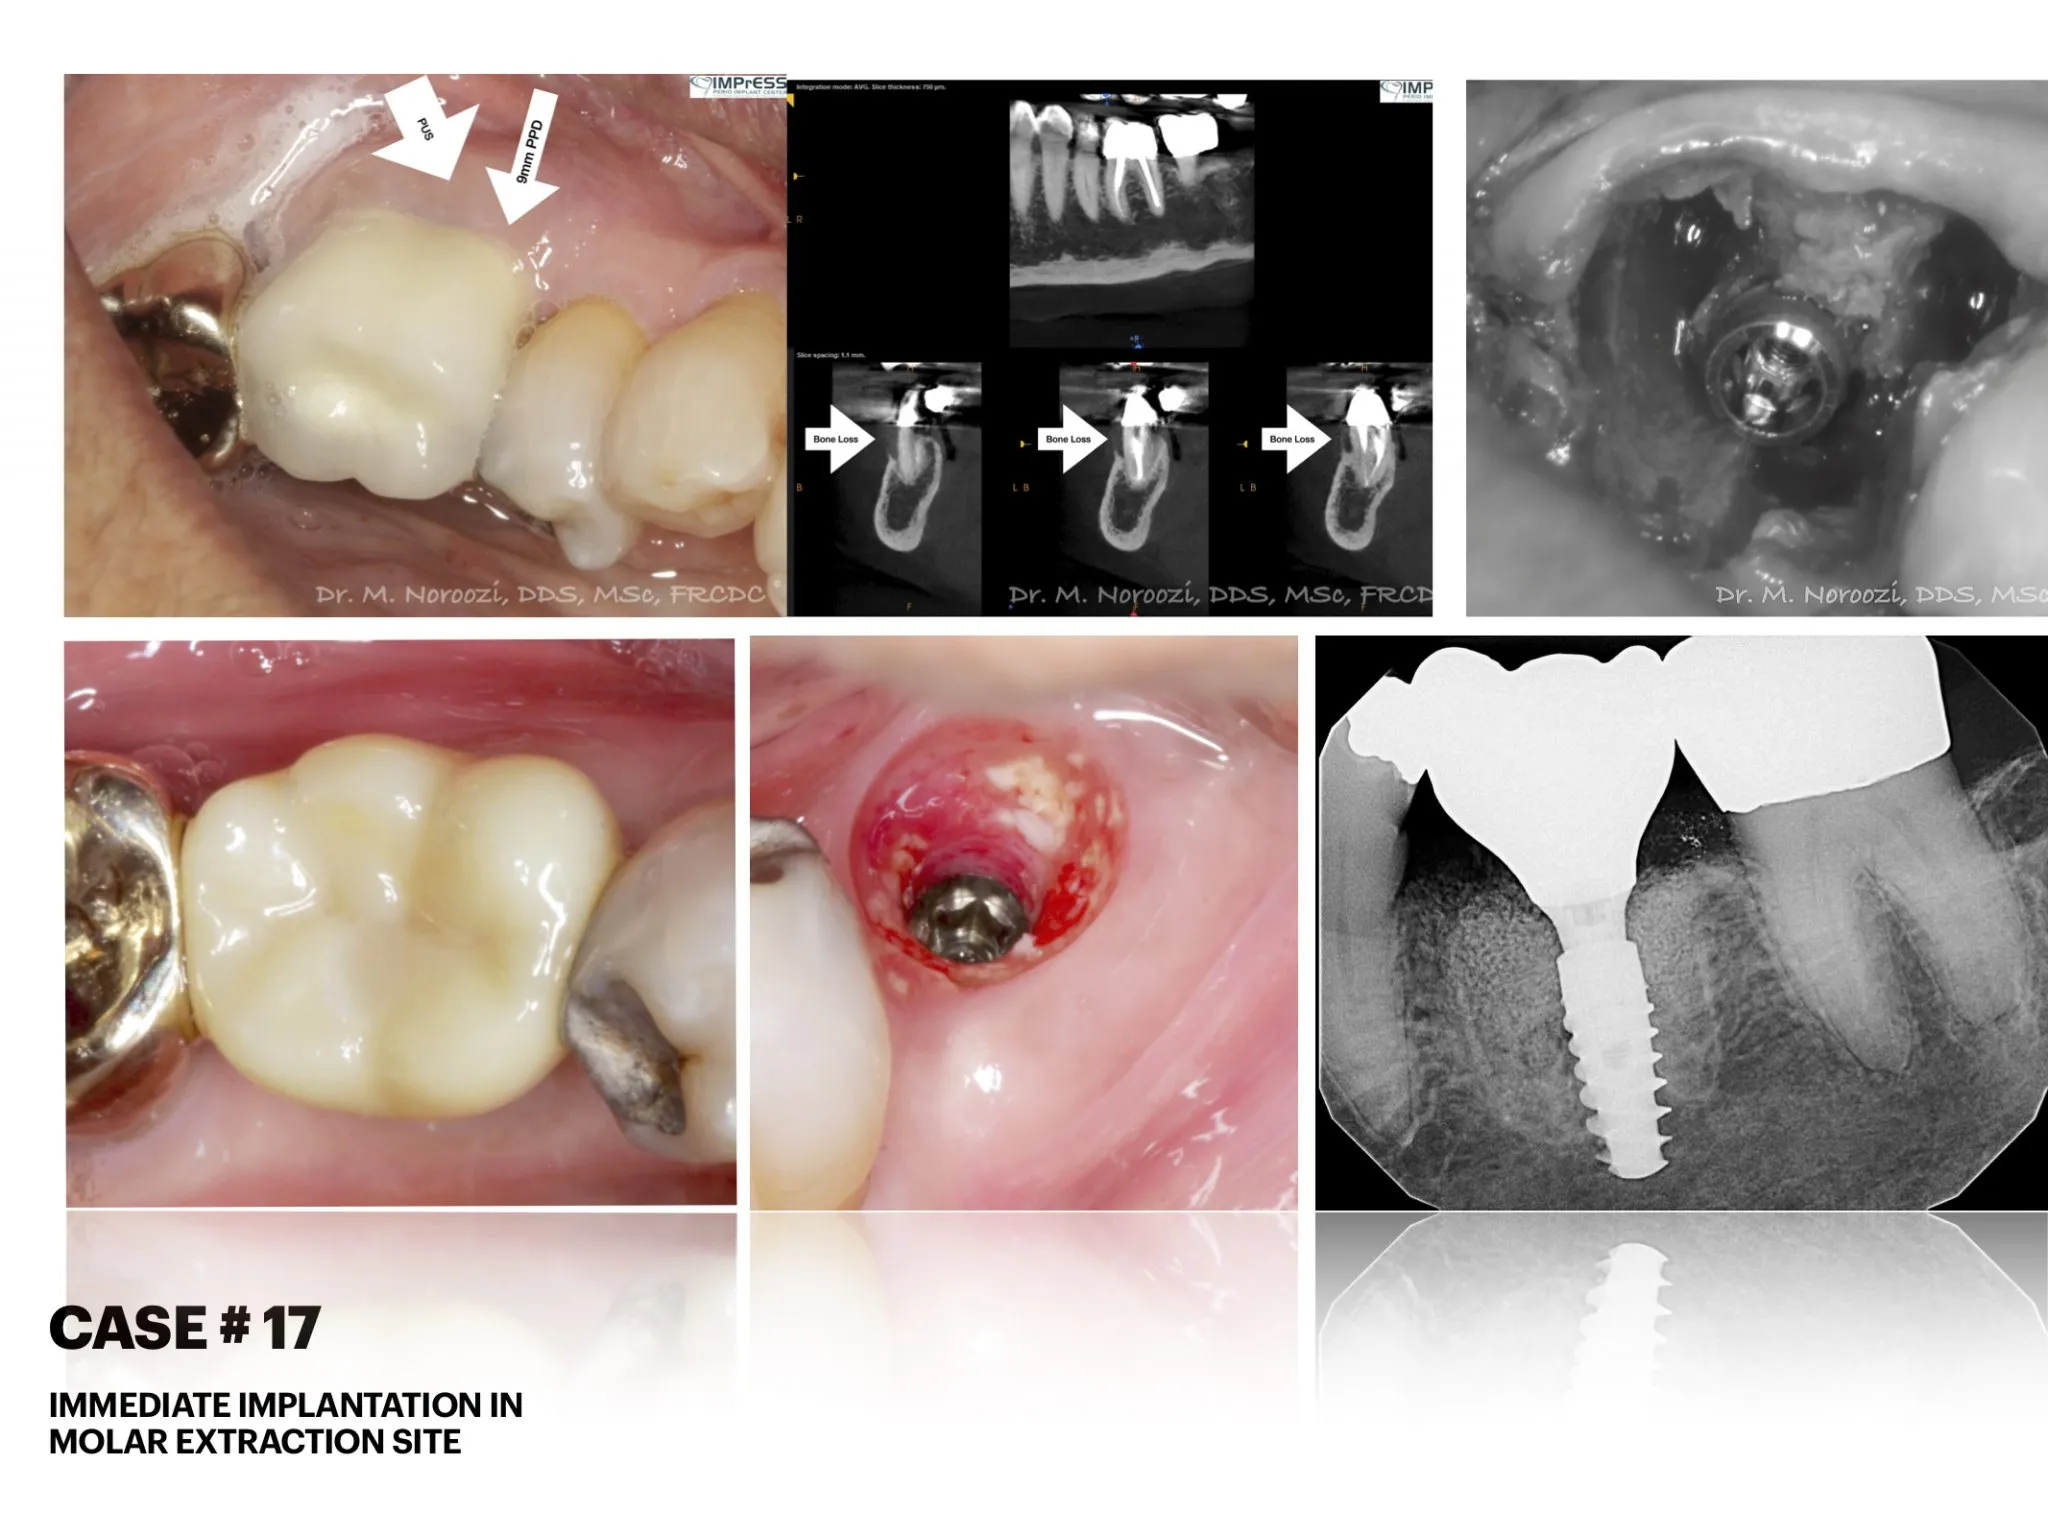

Immediate Implant Placement in Molar Extraction Site

IMPrESS Perio Implant Center Dr. Noroozi Vancouver Periodontist Implant Specialist Burnaby BC

immediate implant placement in molar site Dr. Noroozi